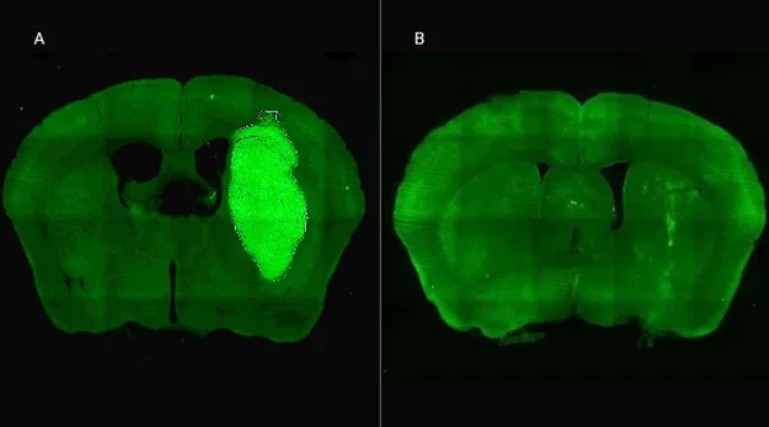

Candolfi y colegas utilizaron una terapia génica experimental basada en una molécula muy pequeña o péptido llamado P60, desarrollado por Juan José Lasarte en la Universidad de Navarra, en España, que atraviesa la membrana celular e inhibe la proteína Foxp3. “Cuando en experimentos de laboratorio bloqueamos Foxp3 utilizando P60, la respuesta de las células de glioblastoma a la radioterapia y a una variedad de drogas quimioterapéuticas mejoró notablemente”, destacó la investigadora del CONICET.

Además, P60 tuvo efectos antitumorales directos, reduciendo la viabilidad y la migración de las células de glioblastoma e inhibiendo la proliferación de células endoteliales que son clave para la progresión del tumor. Para evaluar estos efectos, los autores del estudio utilizaron una variedad de modelos celulares murinos (de roedor) y humanos. “En particular, los cultivos derivados de biopsias de pacientes con glioblastoma desarrollados por nuestro colaborador Guillermo Videla Richardson, del Instituto FLENI, son muy útiles para representar la heterogeneidad de estos tumores”, indicó Candolfi.